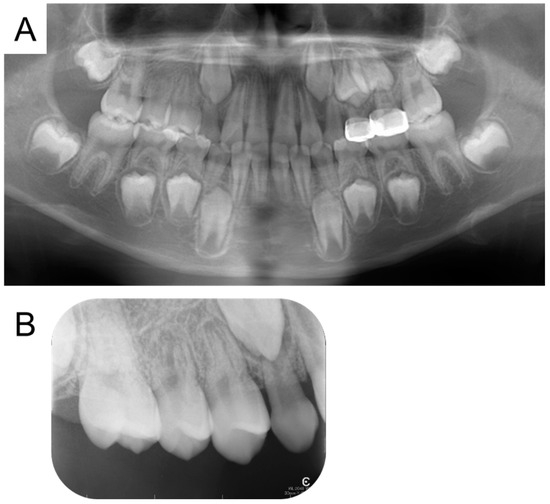

2. Detailed Case Description

| Present case | #55 | Mesio-buccal canal | Reamer | 17 months | Enamel hypoplasia |